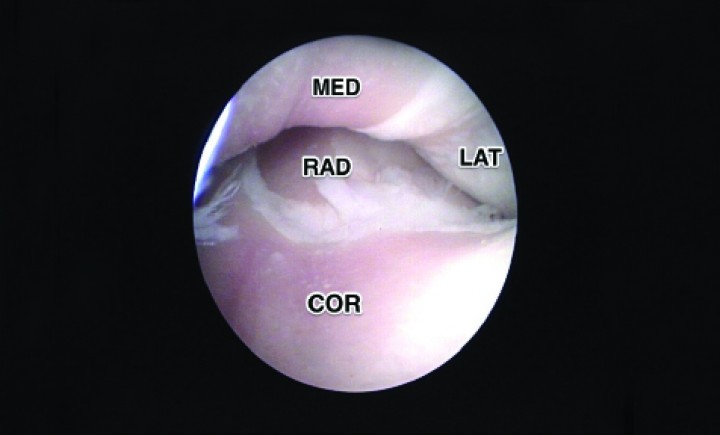

Las repercusiones a nivel terapéutico son importantes porque pocos beneficios pueden obtenerse del tratamiento artroscópico en estos animales más allá de un lavado articular, ya que no se puede esperar una regeneración cartilaginosa con la simple estimulación del hueso subcondral en áreas tan extensas (Fig. 10). Sin embargo, se han desarrollado técnicas quirúrgicas que alteran la biomecánica articular, desplazando las fuerzas al compartimento lateral, que podrían ayudar clínicamente en las lesiones cartilaginosas del compartimento medial.[ Wendelburg K, Beale B. Medium and long term evaluation of sliding humeral osteotomy in dogs. Vet Surg 2014; 43: 804-813. [PubMed] , Pfeil I, Böttcher P, Starke A. Proximal abduction ulna osteotomy (PAUL) for medial compartment diseases in dogs with ED. Proceedings of the 16th European Society of Veterinary Orthopaedics and Traumatology Congress; 2012, Bologna, September, pg 12-14. ]

<div class=\"Basic-Text-Frame\">

<p>Imagen de artrografía. Síndrome del compartimento medial (MED) severo y del compartimento lateral (LAT) moderado. La extensión de la erosión alcanza también desde el coronoides (COR) hasta la cabeza del radio (RAD).</p>

</div>

Figura 10

Imagen de artrografía. Síndrome del compartimento medial (MED) severo y del compartimento lateral (LAT) moderado. La extensión de la erosión alcanza también desde el coronoides (COR) hasta la cabeza del radio (RAD).